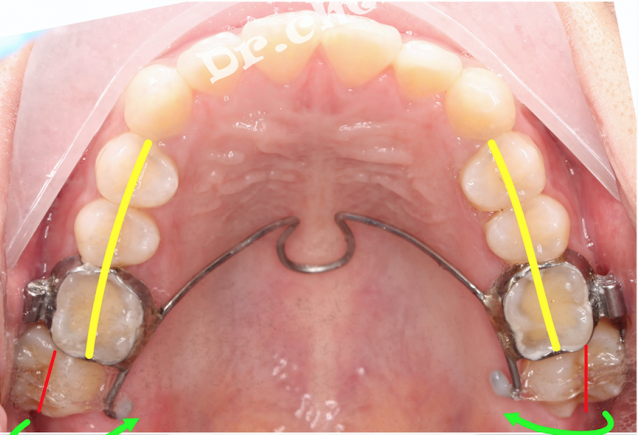

②上排牙被缩弓,拔掉两颗正畸牙,其中第二磨牙未加入正畸,导致双侧锁颌

①智齿不拔(否则会导致正畸结束后第二磨牙的咬合力大大减弱)

可以看出向下的力过猛,牙根露出来了,所以向下的力要足够的小,初期矫治以向内的力为主。(理想情况是切线力)

搞清楚力臂和支点的缺点(如果支点是牙颈,会引发骨开窗)